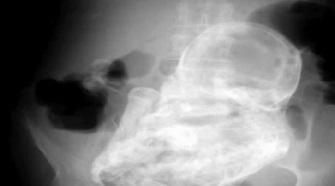

Aucune échographie n'avait révélé sa grossesse. Mais la radiographie réalisée à l'hôpital présente une étrange tâche blanche. Il s'agit d'un foetus de 32 semaines qui s'est « fossilisé ». Il s'agit du deuxième cas répertorié en Colombie. Selon El Tiempo, la vieille femme compte se faire opérer afin d'extraire ce foetus, composé en grande partie de tissus morts.

Ce phénomène s'appelle le lithopédion ou « bébé de pierre » (du grec lithos, pierre, et pais, enfant) et il est excessivement rare. Selon le journal de la Royal Society of Medicine, 300 cas seulement ont été enregistrés dans le monde. Il s'agit d'une grossesse extra-utérine, c'est-à-dire qu'elle se produit dans l'abdomen. Cette grossesse n'arrive pas à terme. Au lieu d'être expulsé, le foetus reste et se calcifie avant de se « fossiliser ».